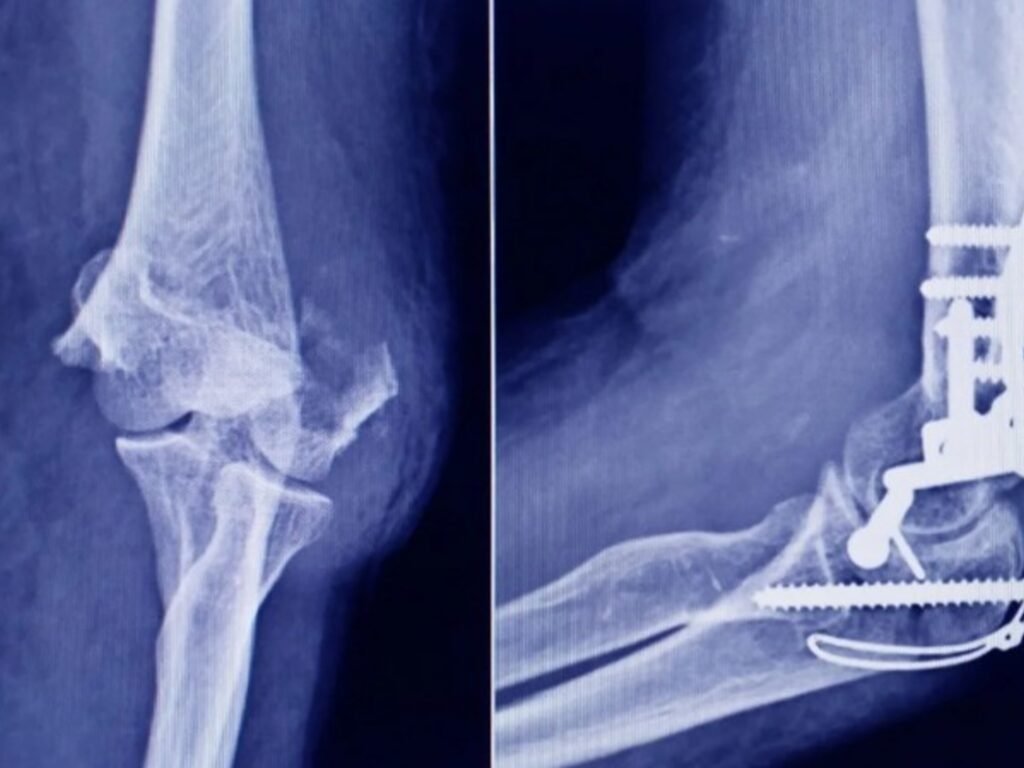

Uncategorized La ANMAT advierte que un tornillo utilizado en cirugías traumatológicas fue falsificado adminhace 4 mesesMenos de 1 min21,0 Vistas Lo encontraron en una ortopedia de San Miguel de Tucumán. El organismo gubernamental marcó las diferencias entre el producto original y el falsificado. Acciones: TE RECOMENDAMOS Uncategorized ¿A qué hora juega Colombia vs. Canadá por el Clásico Mundial de Béisbol 2026? Horarios por país y dónde ver EN VIVO el partido este sábado 7 de marzo hace 2 meses Uncategorized Venezuela-Estados Unidos HOY, EN VIVO: últimas noticias del conflicto entre Maduro y Trump, este domingo 28 de diciembre hace 4 meses Uncategorized La sorprendente decisión de Guardiola en la previa del choque clave del Manchester City vs Real Madrid por la Champions League hace 2 meses Uncategorized Ryan Castro & Gangsta Snatch First No. 1 on Latin Airplay With Kapo Collab ‘La Villa’ hace 1 mes Uncategorized Ashley Tisdale & Hilary Duff’s Mom Group Drama Explained hace 4 meses